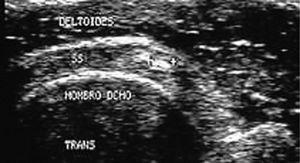

Rotura total

Los signos incluyen adelgazamiento, discontinuidad de la ecogenicidad del tendón e imagen anecoica dentro de la estructura del tendón por el hematoma, y a veces retracción del tendón.

Otros signos son descenso del deltoides, ausencia o no visualización del tendón, signo de la tuberosidad desnuda, irregularidad del reborde humeral y signo del cartílago interfase.

2) Moderada rotura: de 2 a 4 cm (fig. 5).

Figura 5. Rotura total de grosor completo, de moderado tamaño del tendón supraespinoso. Corte longitudinal.